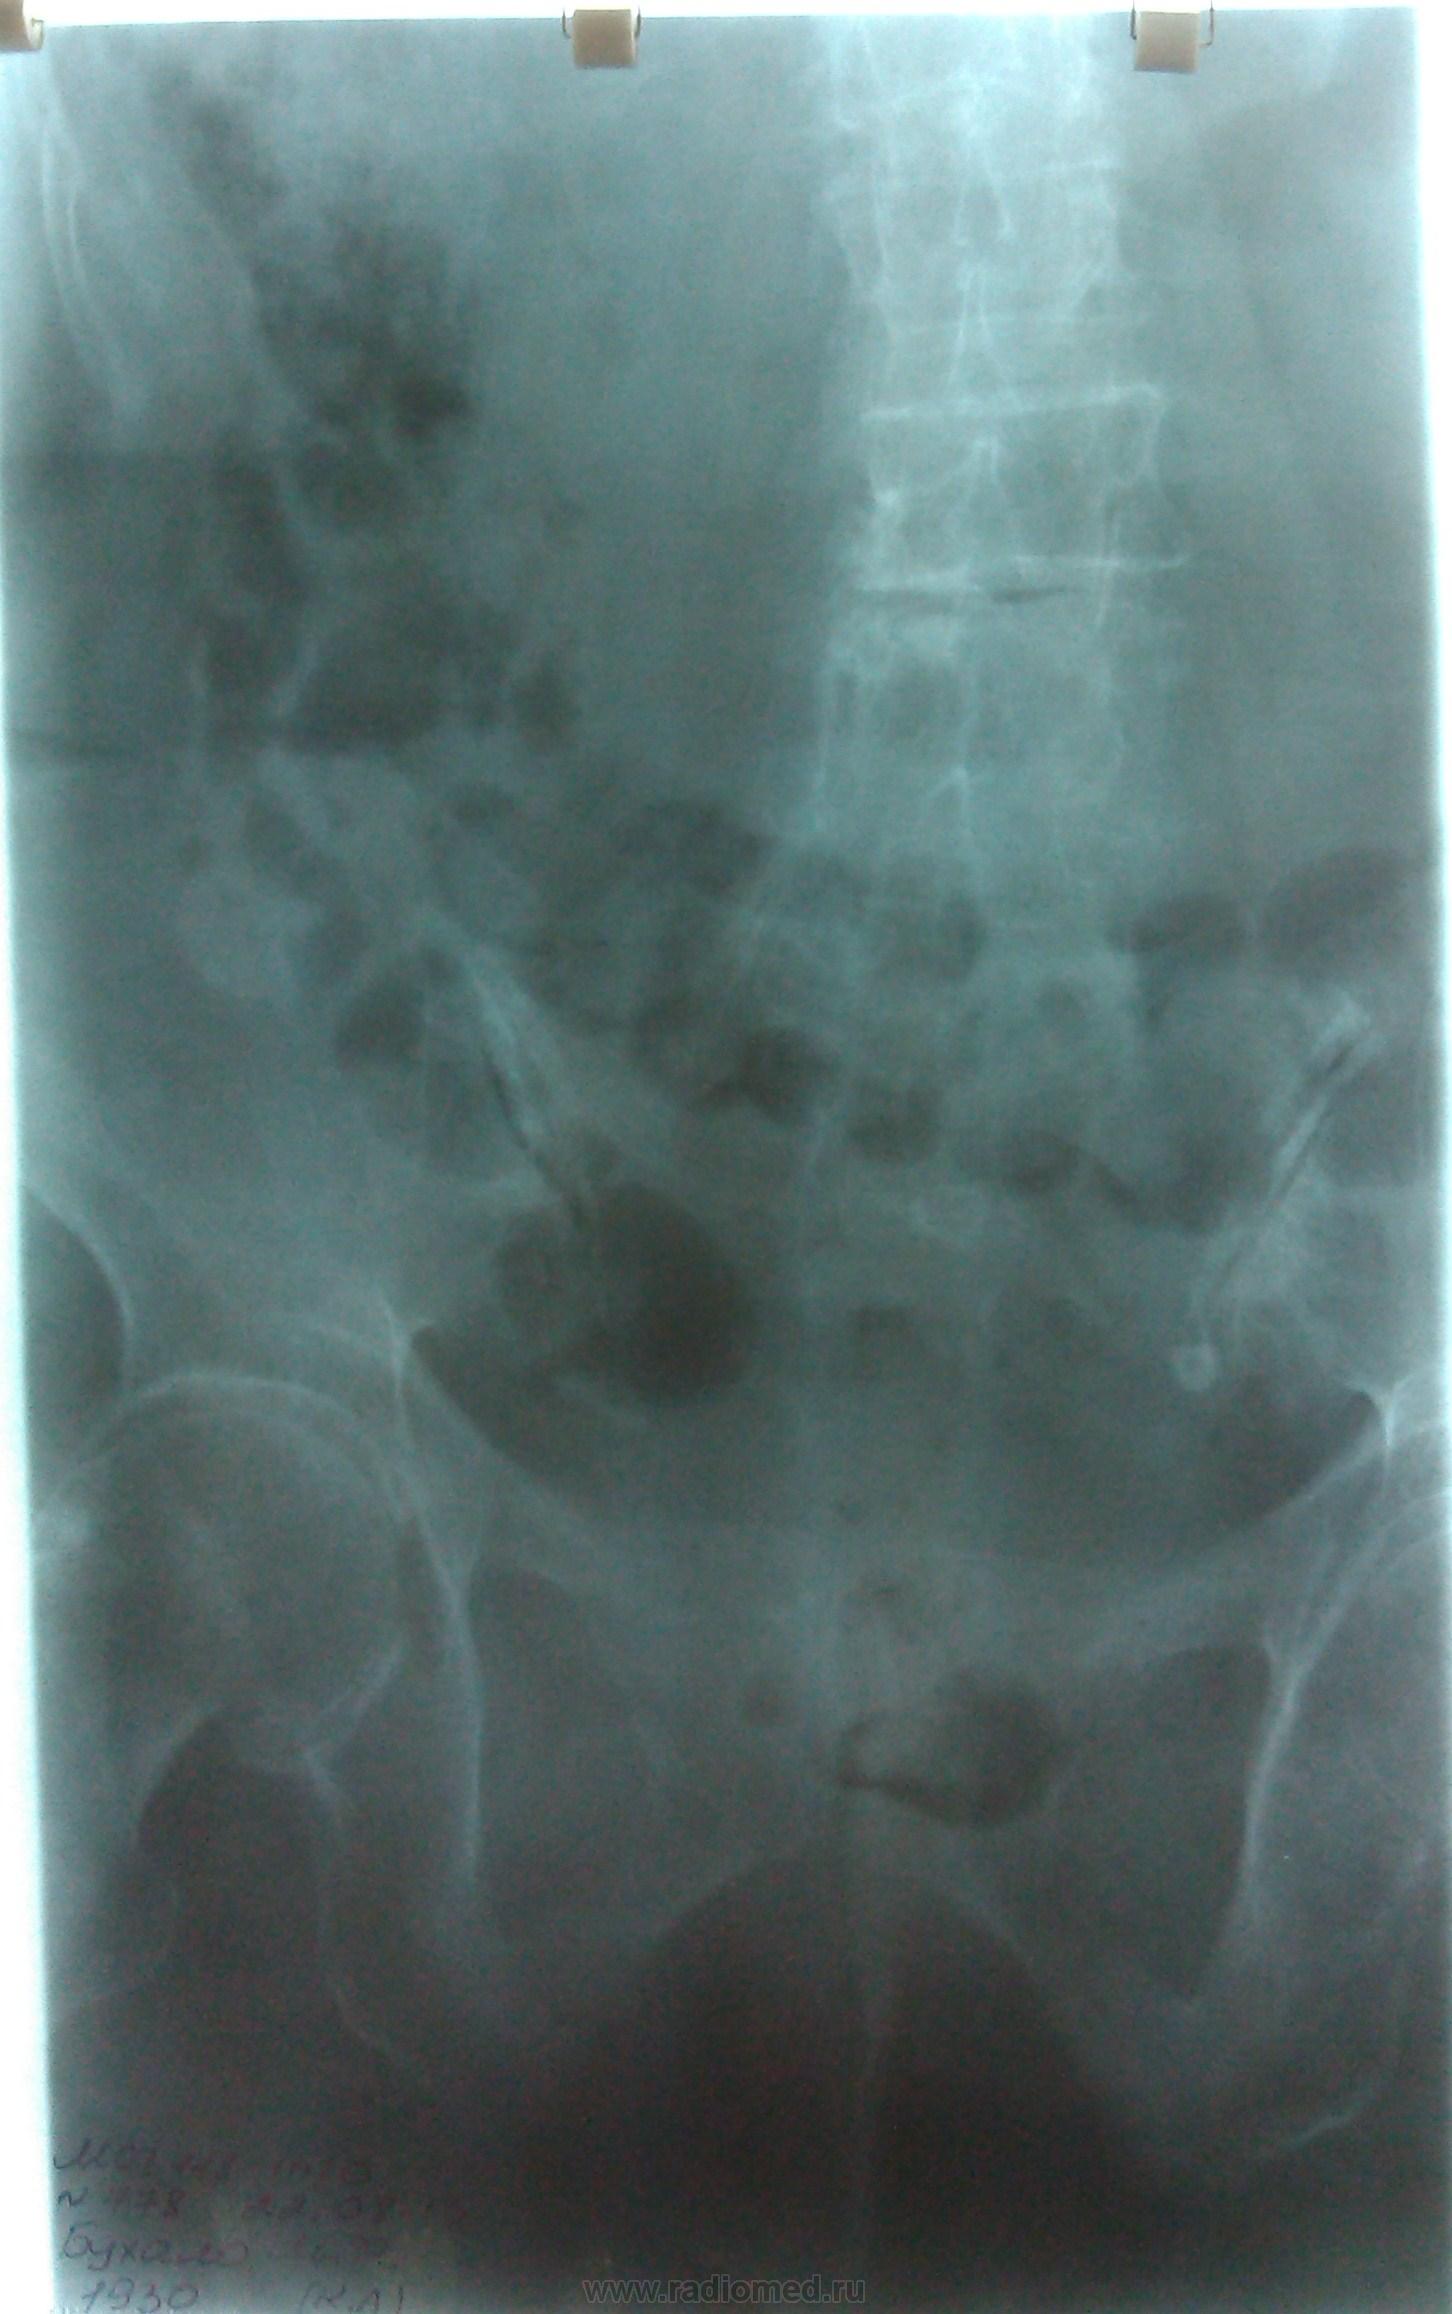

Пациентка, 83 года. DS: ИБС: Атеросклеротический кардиосклероз. Выраженный кифоз грудного отдела позвоночника. Какие мнения по поводу заключения?

Смотрится как релаксация правого купола диафрагмы

Центральный рак нижнедолевого бронха правого легкого, ателектаз нижней доли правого легкого, мтс в кости аксиального скелета грудной клетки.

А спереди в синусе не жидкость? Согласна с релаксацией. А вот кругляш на метастаз тянет. Или периферический?

Как-то слишком округло для ателектаза на боковом снимке, и дуга аорты на месте..

+1. По боковой проекции,  в базальном отделе  кпереди от позвоночника, тень округлой формы- MTS ? Необходимо дообследование, в каком виде выполнить его зависит от возможностей: оптимально КТ грудной клетки. При отсутствии линейная томография на правый корень и структуру округлой тени справа. Находки надо связать с клинико-лабораторными данными.

Господа коллеги, какая релаксация, какая связь с клинико-лабораторными данными?

Посмотрите на ребра...

А как по этим снимкам можно оценить ребра и тем более увидеть в них мтс?

Прямой снимок недоекспонированый. Позвоночника совсем не видно. Да и боковой недостаточно жесткий. Предлагаю начать с переделки снимков. А в целом, подозрения на онко поддерживаю.